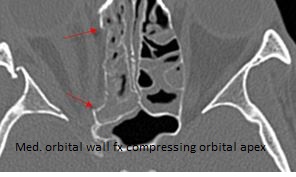

The soft tissues of the orbital apex and the superior and inferior orbital fissures appear abnormal. [Yes/No]

There is evidence of bony injury along the walls and/or floor of the orbit. [Yes/No]

The mesial naso-orbito-ethmoid complex is fractured. Specifically, there is bony injury of the nasal bones or the frontal process of the maxilla and the medial walls of the orbit are abnormal. [Yes/No]